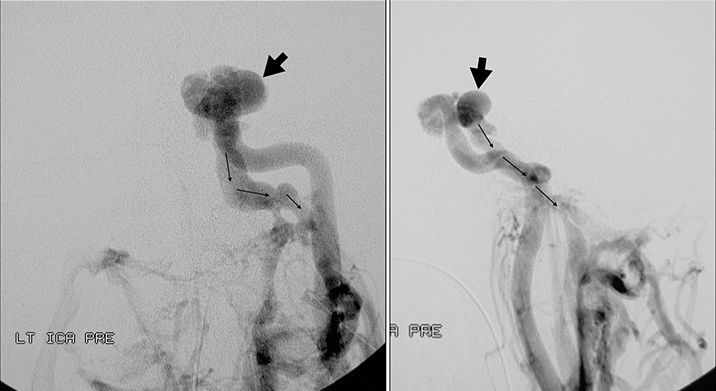

Κλασσική ενδαρτηριακή ψηφιακή αγγειογραφία: Tό πρωτόκολλο περιλαμβάνει τις παρακάτω εκλεκτικές εγχύσεις με τις οποίες διερευνάται το ακριβές σημείο της φίστουλας:

- Σύστοιχη έσω καρωτίδα

- Aντίστοιχη έσω καρωτίδα αρτηρία (προσθοπίσθια λήψη):

- Aντίστοιχη έσω καρωτίδα αρτηρία με ταυτόχρονη πίεση της πάσχουσας κοινής καρωτίδος (προσθοπίσθια λήψη):